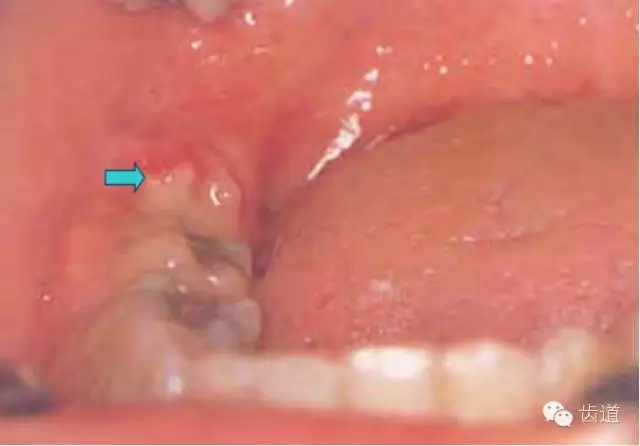

下頜第三磨牙在萌出過程中,由于萌出不全或阻生,牙冠周圍軟組織發(fā)生的炎癥。又稱智齒冠周炎。

1.智齒萌出不全

2.牙冠周圍軟組織紅腫、糜爛、觸痛

3.齦瓣處形成盲袋,內(nèi)有膿性分泌物,有時形成冠周膿腫

4.嚴重時可見咽側(cè)壁及舌腭弓紅腫,患側(cè)頜下淋巴結(jié)腫大、壓痛。